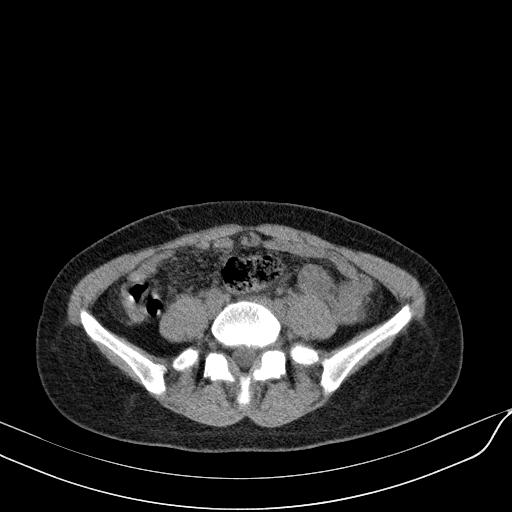

标题: CT23965:无外伤史,下腹痛 [打印本页]

标题: CT23965:无外伤史,下腹痛

肠道未准备,继续往下扫,乙状结肠占位不排除。建议钡灌或结肠镜检查。

乙状结肠占位不排除

未见明显异常改变,做个气钡双重造影除外一下结肠病变,无外伤史为啥不常规喝泛影葡胺水对比剂再扫ct呢?

回肠间质瘤?

肠道肿瘤,建议行钡剂灌肠检查。